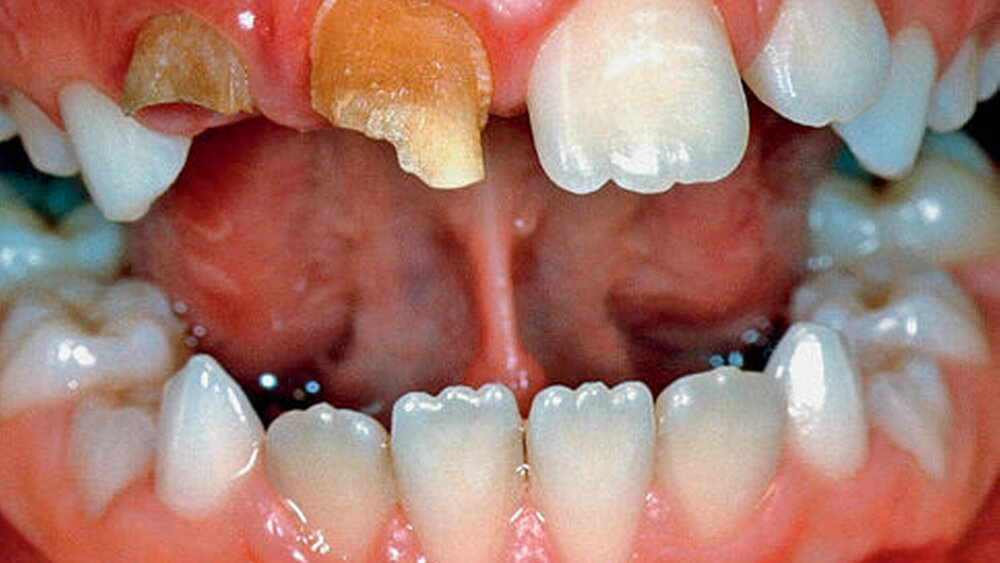

Bei der Odontodysplasie handelt es sich um eine gleichzeitige Schmelz- und Dentindysplasie. So sind Schmelz-, Dentin und Pulpaveränderungen zu erkennen. Die Odontodysplasie (Abbildungen 11 bis 15) ist eine seltene Erkrankung, welche in der Regel an einem oder mehreren Zähnen eines Quadranten auftritt. Diese Erkrankung betrifft vor allem Zähne im Oberkiefer (Abbildungen 11 und 12) und ist etwas häufiger bei Frauen zu beobachten. Sowohl Milchzähne als auch permanente Zähne können davon befallen sein. Genaue Zahlen über die Vorkommenshäufigkeit der Odontodysplasie sind nicht bekannt, da diese Erkrankung so selten ist. Die Ätiologie der Odontodysplasie ist nach wie vor unklar.

Die betroffenen Zähne weisen gelbbraune Verfärbungen auf (Abbildungen 11, 12 und 14) und sind kleiner als normal. Der vorhandene Schmelz ist hypoplastisch und unterverkalkt. Schmelz und Dentin sind sehr weich. Die Zahnkronen sind missgebildet. Die Wurzeln sind in der Regel sehr kurz. Die Zahnoberfläche kann Furchen, Eindellungen und Grübchen aufweisen. Der Durchbruch und die Wurzelbildung der befallenen Zähne sind verzögert. Infolge der stark veränderten Zahnhartsubstanz ist eine stark erhöhte Kariesanfälligkeit vorhanden. Kurz nach dem die betroffenen Zähne die Gingiva durchbrochen haben, kann es deshalb rasch zur Kariesbildung kommen. Daraus resultieren häufig Pulpanekrosen und Abszesse.